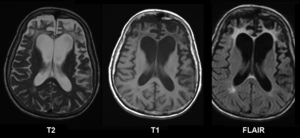

image الإنجليزية

Pick's disease.png

١٬٢٠٠ × ٥٥٢؛ ٢٢٣ كيلوبايت